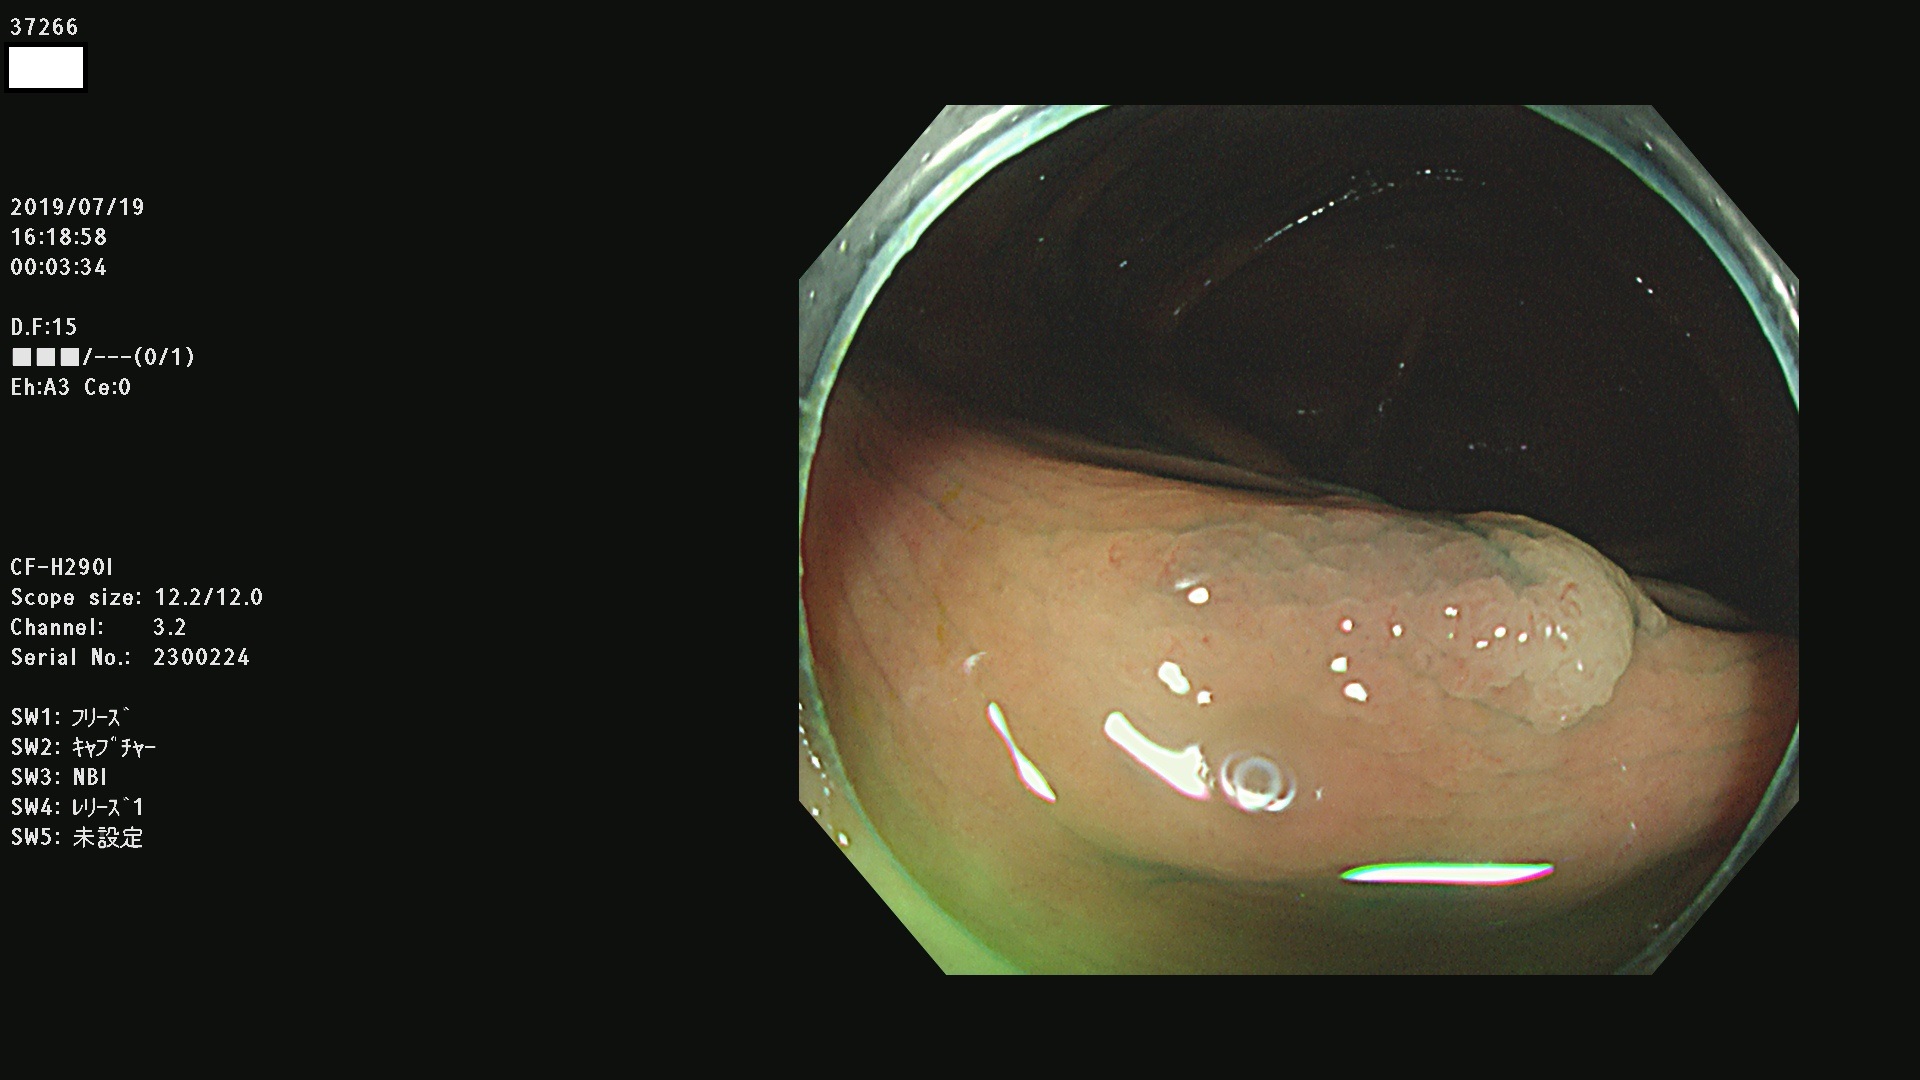

37200 37203 37204 37207 37208 37209 37210 37211 37212 37213 37214 37215 37216 37217 37220 37221 37222 37224 37225 37228 37229 37230 37232 37233 37234 37235 37236 37238 37241 37242 37243 37244 37245(SSAPのみ) 37247 37249 37250 37251 37252(SSAPのみ) 37254 37256 37257 37258 37259 37260(SSAPのみ) 37261(SSAPのみ) 37262 37263 37264 37265 37266 37267 37268(SSAPのみ) 37269 37271 37273 37274 37276 37277 37278 37279 37280 37281 37282 37284(SSAPのみ) 37285 37286 37288 37289 37290 37292 37293 37295 37296 37297(SSAPのみ)

発見困難で危険性の高い平坦型病変(上記100名より抽出)